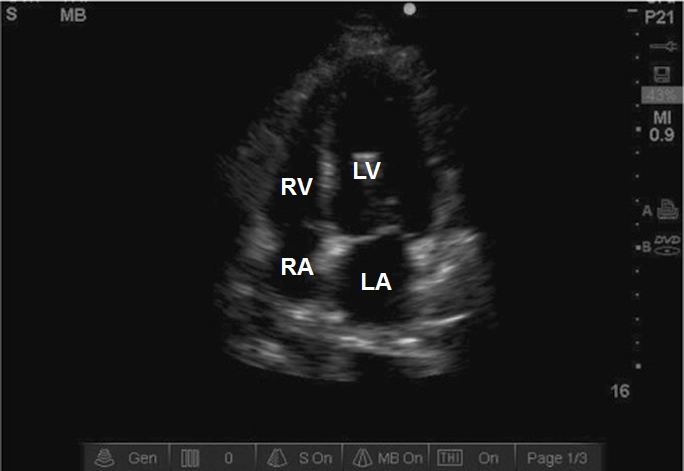

Case 7-3. Apical Four-chamber View

Video 7-3A. While the septum is centrally orientated, the left ventricle is foreshortened. This was the best view that could obtained in this obese patient on ventilatory support, continuous hemofiltration, and high-dose pressors. The intensivist faces major obstacles in obtaining the apical views related to patient habitus, supine position, respiratory translational artifact, and ICU equipment that blocks good scanning position. In this case, there is moderate right ventricular (RV) enlargement with normal RV free wall function. At times, the intra-atrial septum bows into the left atrium, suggesting elevation of right atrial pressures. The subcostal long-axis view would be obligatory alternative view to examine RV wall thickness and septal kinetics.